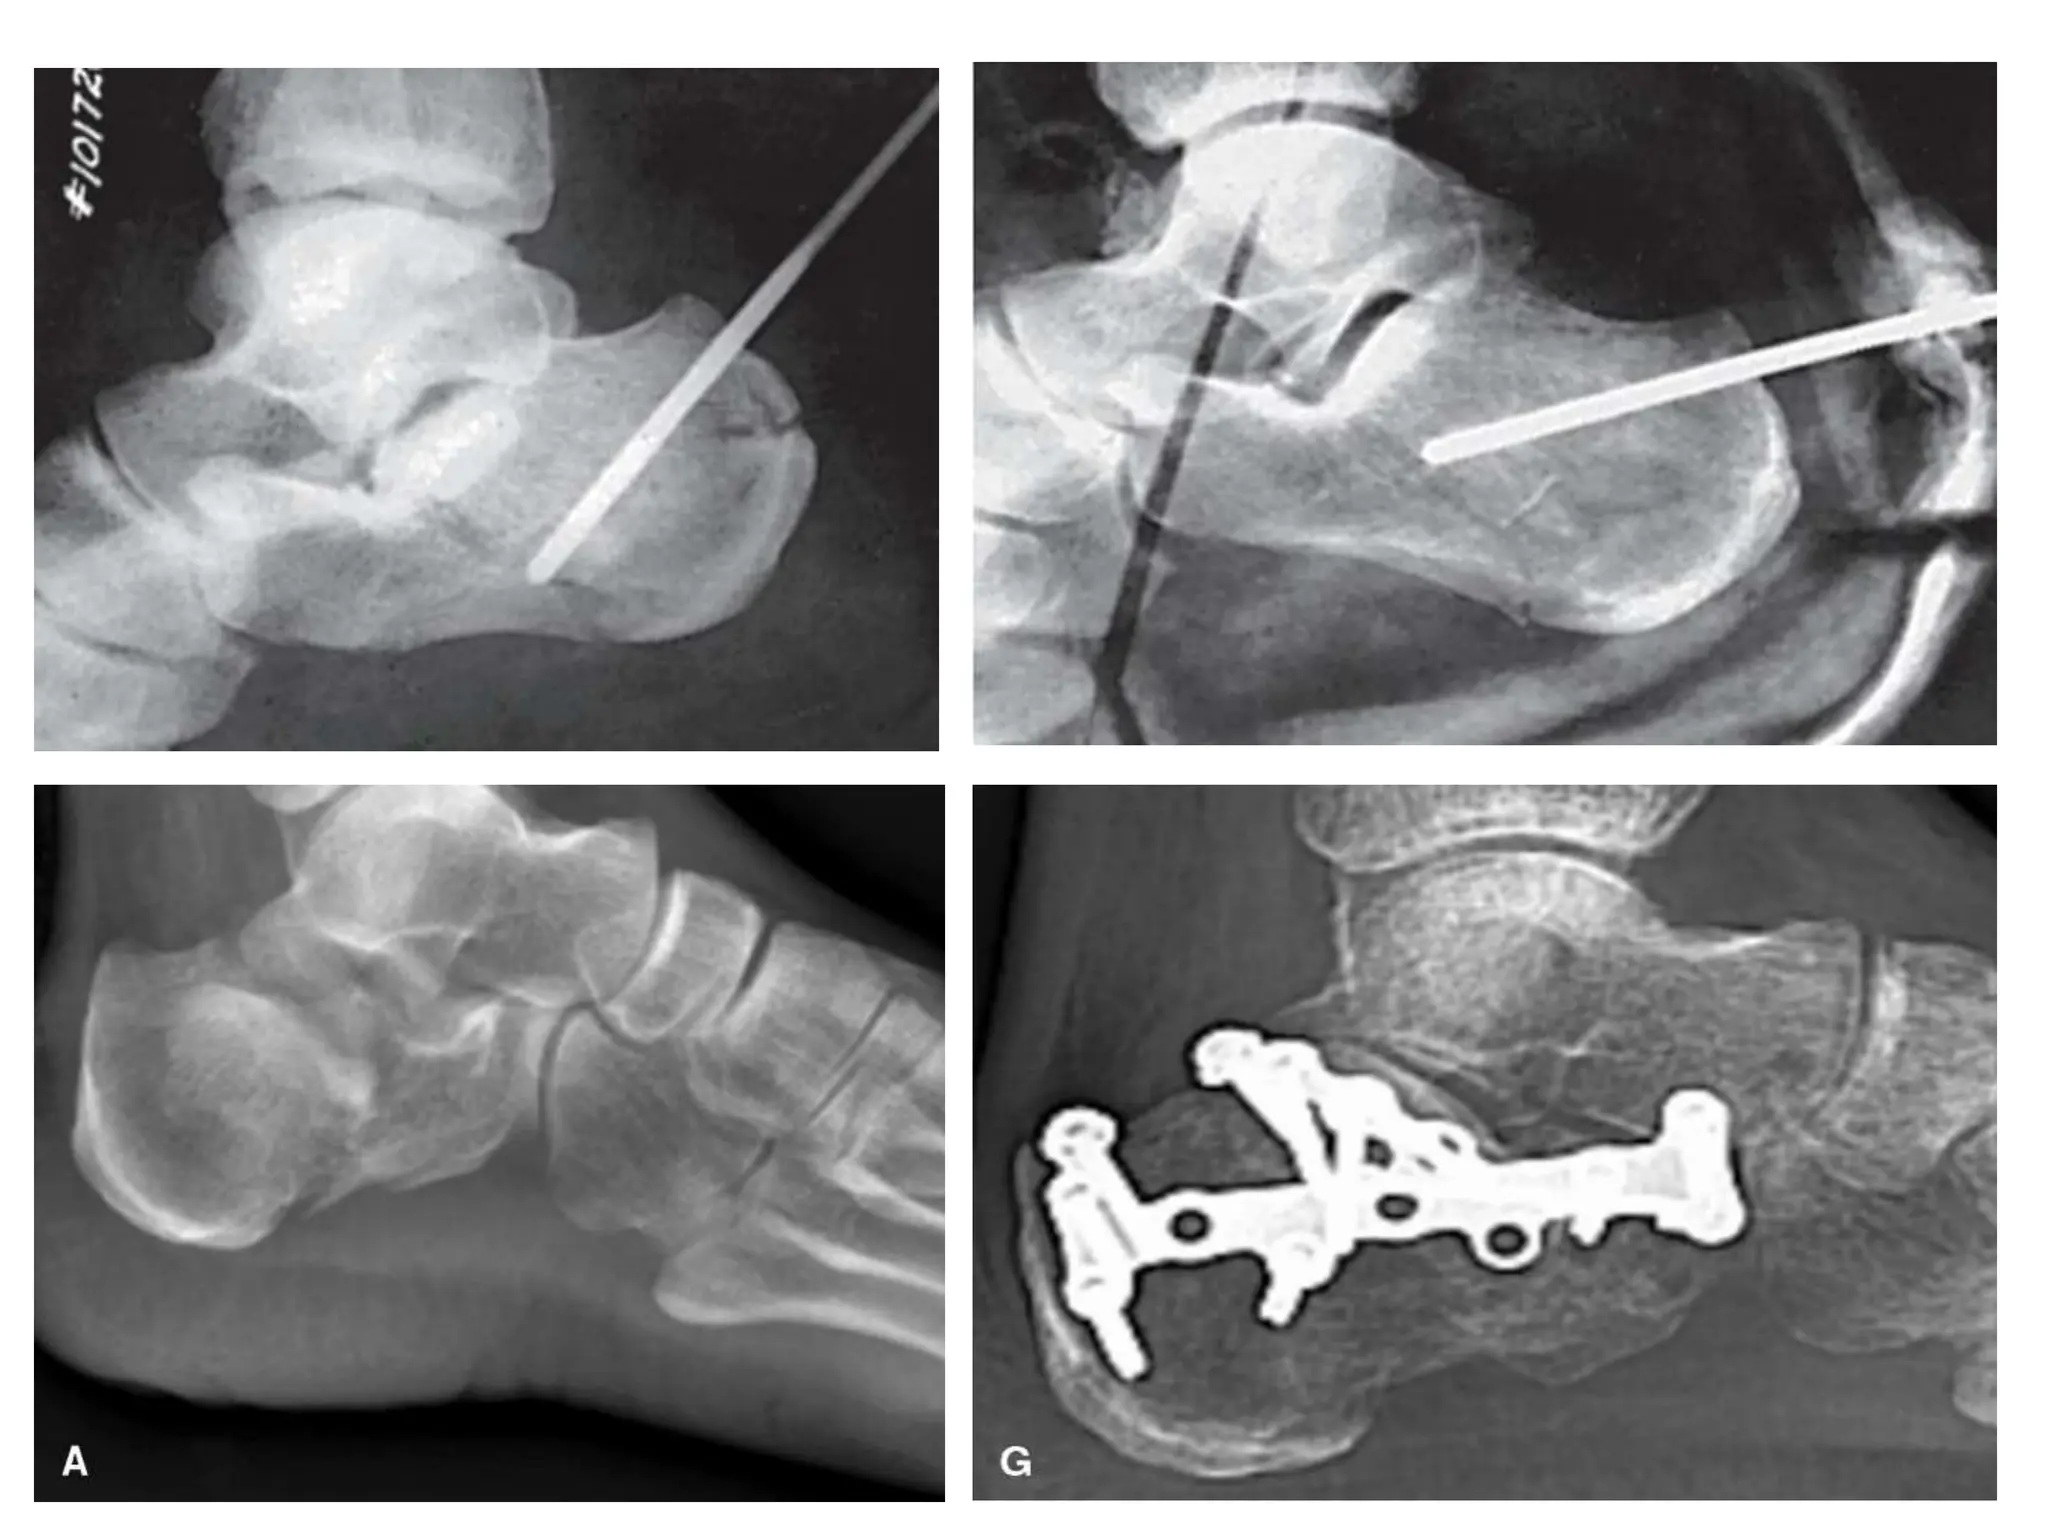

Percutaneous and Minimally Invasive Fixation

• Indications:

 Sanders 2C tongue-type fractures in which the entire

posterior facet is attached to the tongue fragment

 displaced calcaneal tuberosity or beak fractures

 emergent reduction and temporary stabilization of

fractures with severe or impending soft tissue

compromise from displaced fracture fragments

 fractures in patients with relative contraindications to

open surgery, such as heavy smokers or patients

requiring chronic anticoagulation

Fixation of body. A: Lateral wall replaced, and low-profile plate applied. B–D: Radiographs of

final fixation, showing anatomic reduction of the articular surface, anterior process, and

tuberosity